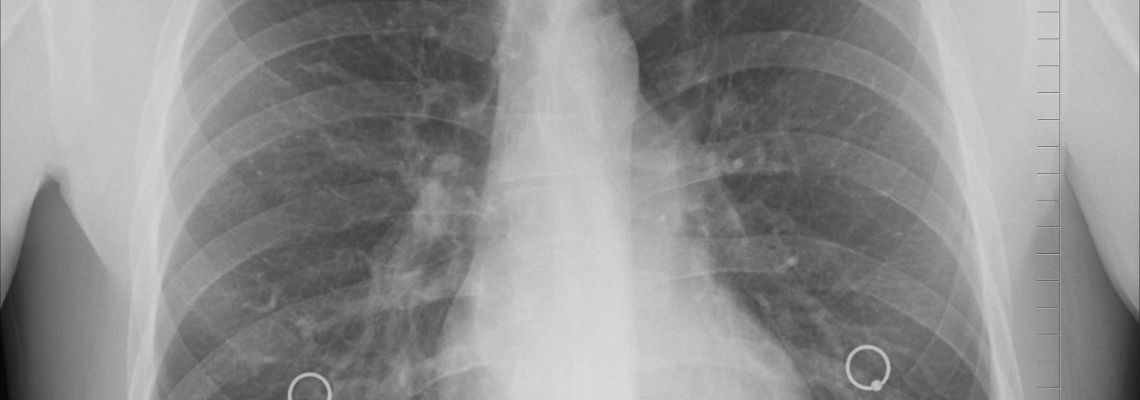

COPD of chronisch obstructief longlijden is een nog altijd fel onderschatte chronische longziekte met als kenmerken ontstekingen aan de luchtweg, luchtwegvernauwing en afbraak van longweefsel. Personen die lijden aan COPD hebben last van kortademigheid en vaak ook van hoesten.

COPD is een verzamelnaam die onder meer chronische bronchitis en longemfyseem omvat. Deze losse termen worden minder vaak gebruikt. Chronische bronchitis duidt op een chronische ontsteking van de bronchiën (de vertakkingen van de luchtpijp naar de longen). Daardoor wordt er meer slijm aangemaakt dat moet worden opgehoest. Naast deze ontsteking is er ook progressieve vernauwing van de kleinere luchtwegen zodat ademhalen moeilijker wordt. Bij longemfyseem gaan er langzaam steeds meer longblaasjes verloren. De longblaasjes zorgen ervoor dat zuurstof kan worden opgenomen. Hoe minder longblaasjes er zijn, hoe moeilijker dit wordt.